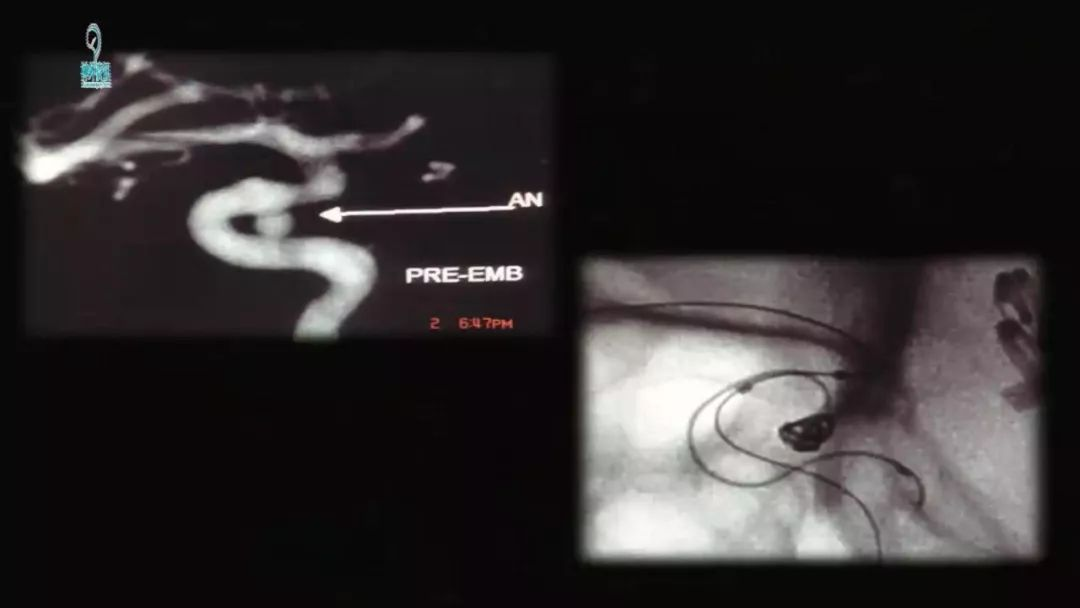

王智教授:从复合型医生的角度看待脑动脉瘤治疗的选择